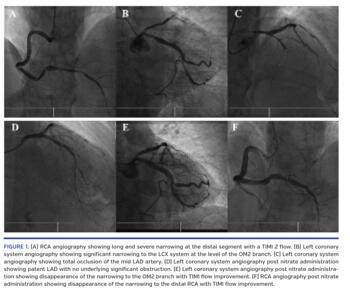

A 64-year-old male with a history of diabetes mellitus and hypertension presented to our institution for recurrent angina occurring mainly at rest. He had no history of current or prior smoking, cocaine, or other drug abuse. Electrocardiogram (ECG) and echocardiography were normal. It was agreed with the patient to proceed with elective coronary angiogram. The procedure was performed through right radial access. The first artery to be engaged was the right coronary artery (RCA) (Figure 1A; Video 1), which was the dominant artery and tortuous. It showed long and severe narrowing at the distal segment with Thrombolysis in Myocardial Infarction (TIMI) 2 flow. During the procedure, the patient suddenly developed chest discomfort concomitantly with ischemic ECG changes. Hemodynamic parameters remained stable. The left coronary system showed significant narrowing to the left circumflex (LCX) system at the level of the second obtuse marginal (OM2) branch (Figure 1B; Video 2) and total occlusion of the mid left anterior descending (LAD) coronary artery (Figure 1C; Video 3). Intracoronary nitrate injection was performed. Immediate pain relief occurred and the ECG normalized. Further selective coronary injections showed patent LAD (Figure 1D; Video 4) with no underlying significant obstruction, and the narrowing to the OM2 branch (Figure 1E; Video 5) and distal RCA (Figure 1F; Video 6) disappeared. The caliber of the LCX system and the RCA became larger, and TIMI flow improved. Vasodilator treatment with calcium-channel blockers was initiated, and the patient remained symptom free at 1-year follow-up exam.

Coronary artery vasospasm, or Prinzmetal angina, is a constriction of the coronary arteries that can cause complete or near-complete occlusion of the vessel. It remains a challenging diagnosis of spontaneous brief episodes of chest pain, and is usually misinterpreted as acute coronary syndrome. Usually, Prinzmetal angina affects only one coronary vessel; however, in the case herein, it occurred simultaneously in three coronary arteries, and was totally relieved after nitrate administration.